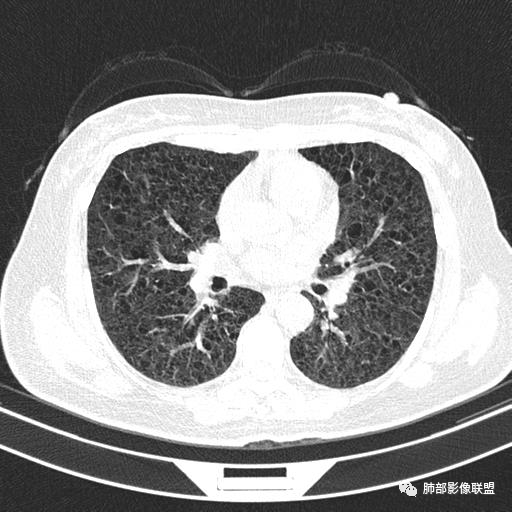

中年女性,不吸烟

双肺弥漫囊腔,累及肋膈角,囊腔形态相对规则单一。

CT平扫示双肺弥漫分布大小不等囊状薄壁透光区,无内、中、外带分布差异,间质稍示增厚。拟LAM

中年女性育龄期妇女,咳嗽气喘,无吸烟史,有苯吸入史。影像:双肺弥漫均匀小囊腔,无明显分布优势,囊腔形态欠规则,壁薄,部分囊腔边缘血管征,伴双肺弥漫磨玻璃影,无结节,考虑lam,鉴别苯中毒肺损伤,囊腔多有分布优势,小叶中心分布为主,形态规整等

双肺弥漫大小不一薄壁含气囊腔,囊间肺组织正常,正常肺背景,肺尖肺底受累;青年女性,气喘,支持LAM

双肺多发大小相近的囊状影,分布趋势趋于一致,中年女性,考虑LAM。部分囊内见血管及分隔影,小叶中心性肺气肿代排

CT表现:双肺弥漫大小不等的薄壁囊腔,囊壁<2mm,外形规则,血管影多位于囊腔周围,囊腔之间肺组织正常,随着疾病进展到晚期,囊腔变大、增多,不可胜数,囊腔可融合成较大的囊,与肺气肿相似,形成间质性肺纤维化。部分病例可出现结节影。